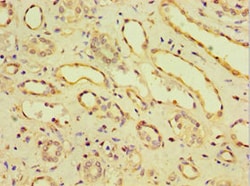

CDH11 Polyclonal Antibody for Western Blot, IHC (P), IP, ELISA

| ELISA, Immunohistochemistry (Paraffin), Immunoprecipitation, Western Blot | |